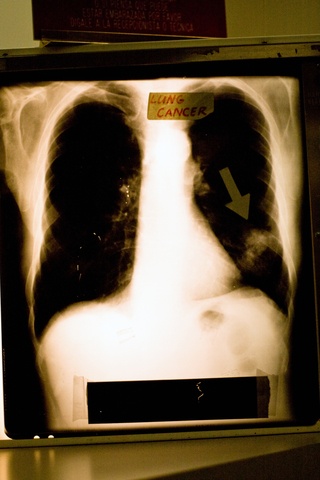

Smoking & Lung Cancer:

Cigarette smoke is linked to about 80% to 90% of lung cancers, cigars and pipes also increase the risk of lung cancer.

Cigarettes contain over 7,000 chemicals, and many are poisons, these chemicals can damage your lung tissue and infect it with carcinogens.

Carcinogens are cancer-causing substances that are found in cigarettes (cigars and pipes) as well as air pollutants.

Common Lung Cancer Symptoms:

- Cough

- Shortness of breath

- Excess mucus

- Reoccurring respiratory infections

- Pain in chest